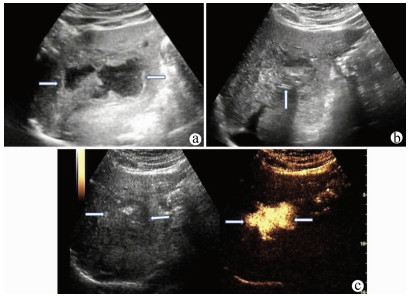

肝病超声诊断指南

中华医学会超声医学分会, 中国研究型医院学会肿瘤介入专业委员会, 国家卫生和健康委员会能力建设和继续教育中心超声医学专家委员会

2021, 37(8): 1770-1785. DOI: 10.3969/j.issn.1001-5256.2021.08.007

摘要(3068) HTML (6587) PDF (9311KB)(804)

超声检查无创、实时、价廉,无辐射、便于反复进行,是最常用的肝脏影像学检查方法。近年来,超声检查新技术如超声造影、弹性成像发展迅速,可有效鉴别肝内占位性病变性质、评估肝纤维化和门静脉高压程度以及监测肝病治疗效果,在临床肝病及其介入治疗中发挥重要诊断价值。本指南规范了肝病多模态超声技术(灰阶超声、彩色多普勒超声、超声造影、弹性超声)检查的仪器调置、患者准备及医生检查方法;对肝脏弥漫性病变(炎性病变、纤维化、硬化)、多种占位性病变及肝病介入操作的多模态超声技术诊断标准进行了定义和规范,同时推荐了超声监测周期及肝脏疾病超声诊断报告书写规范。